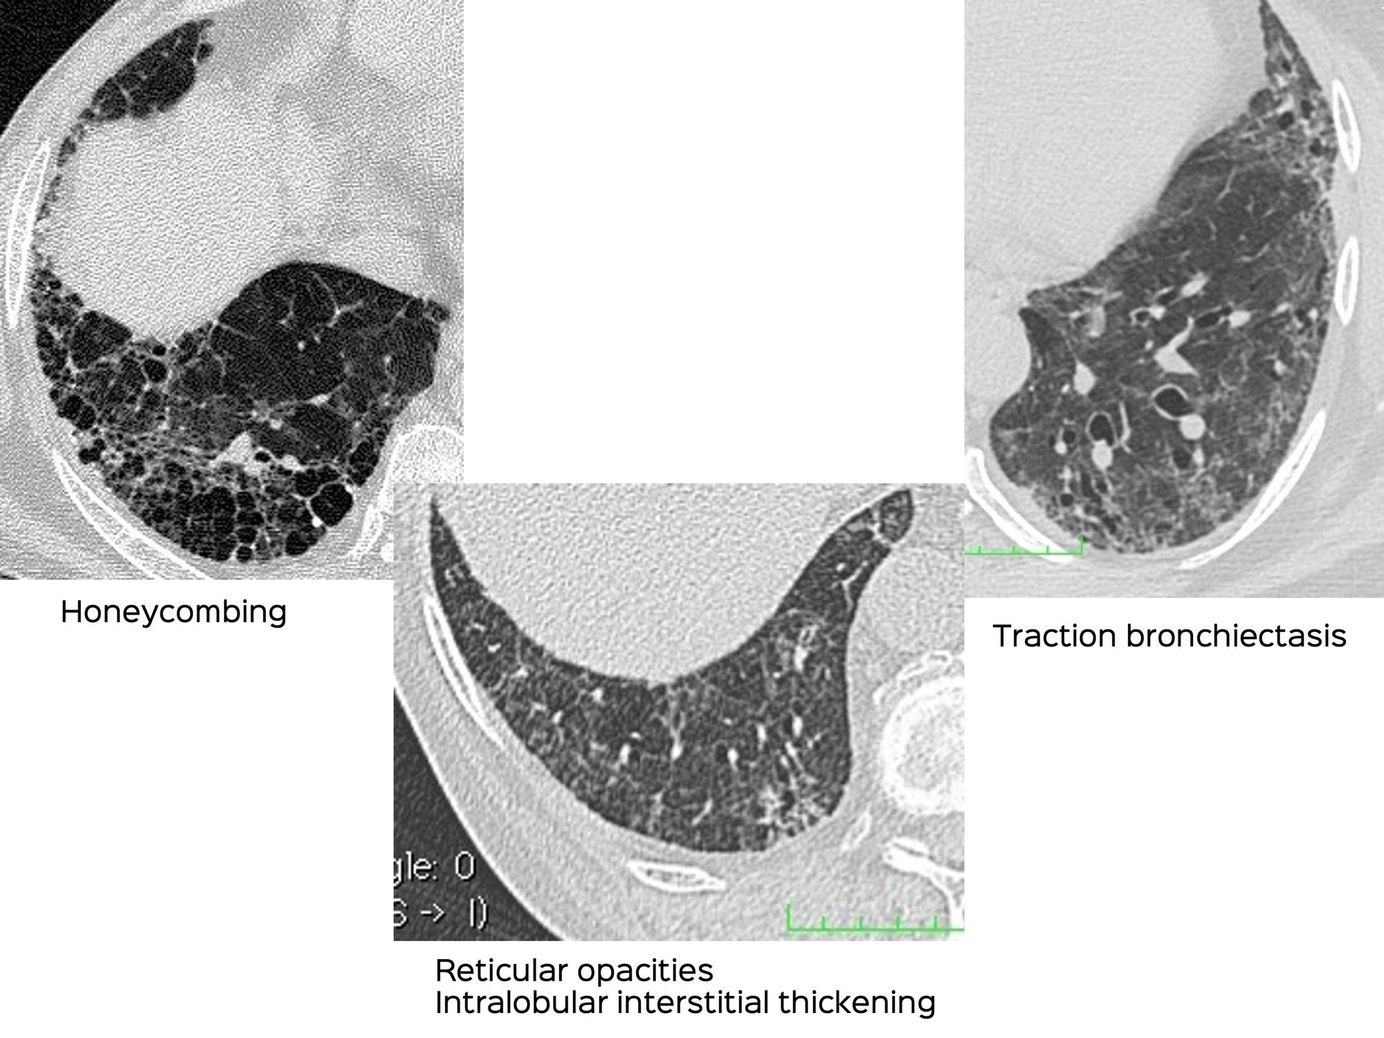

Snippet 01: Differentiating Traction Bronchiectasis from Honeycombing Members Public

Many radiologists & physicians have difficulty differentiating traction bronchiectasis from honeycombing. The post and video explain how to do this.

Bhavin Jankharia

Interstitial Lung Disease